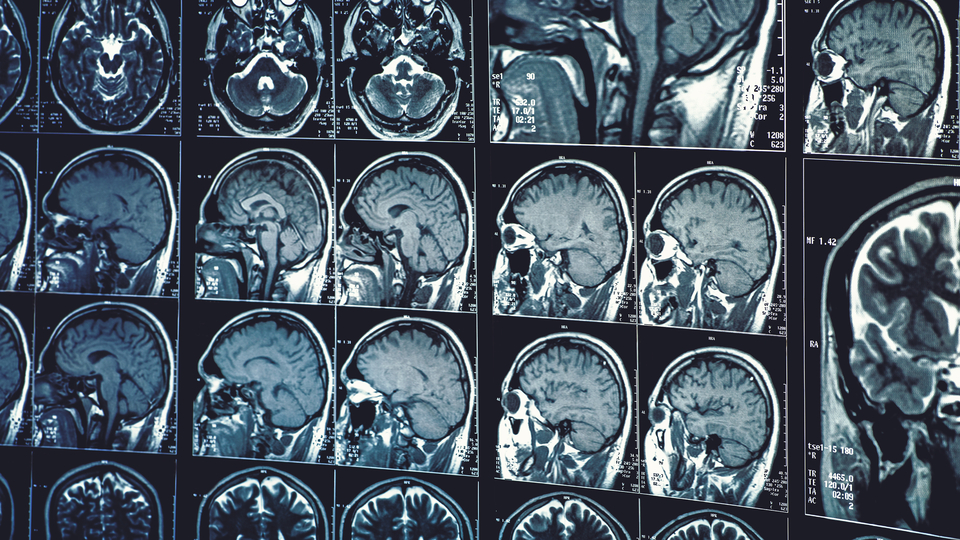

Yapay zeka artık hayatın birçok alanında kullanılıyor. Tıpta özellikle nörolojik hastalıkların tanısında yapay zekayı kullanan OMÜ Tıp Fakültesi Nöroloji Anabilim Dalı, çalışmalarına devam ediyor.

Nörolojik hastalıklarda Alzheimer, Parkinson, MS veya sinir, kas hastalıklarıyla ilgili yapay zeka çalışmalarımız var. Burada özellikle emar (MR) görüntülerini, beyin MR'ı veya omurilik MR'ı görüntülerini makineye tanıtarak yapay zeka aracılığıyla bu görüntünün hastalık olabilir veya beyin hangi bölgesinde bir etkilenme olabiliri makineye söyletmeye çalışıyoruz. Özellikle hastaların ses analizleri ve yürüme analizleri ekleyerek hastalarda tanıya varmaya çalışıyoruz. Baktığımızda yapay zekanın yüzde 90'ın üzerinde bazen yüzde 95'lerde doğru bir tanı koyabildiğini, ayırıcı tanı yapabildiğini ve hastalığın seyri ile ilgili önemli bilgiler verdiğini görüyoruz. Yapay zeka şu anda gelişme aşamasındadır" dedi.